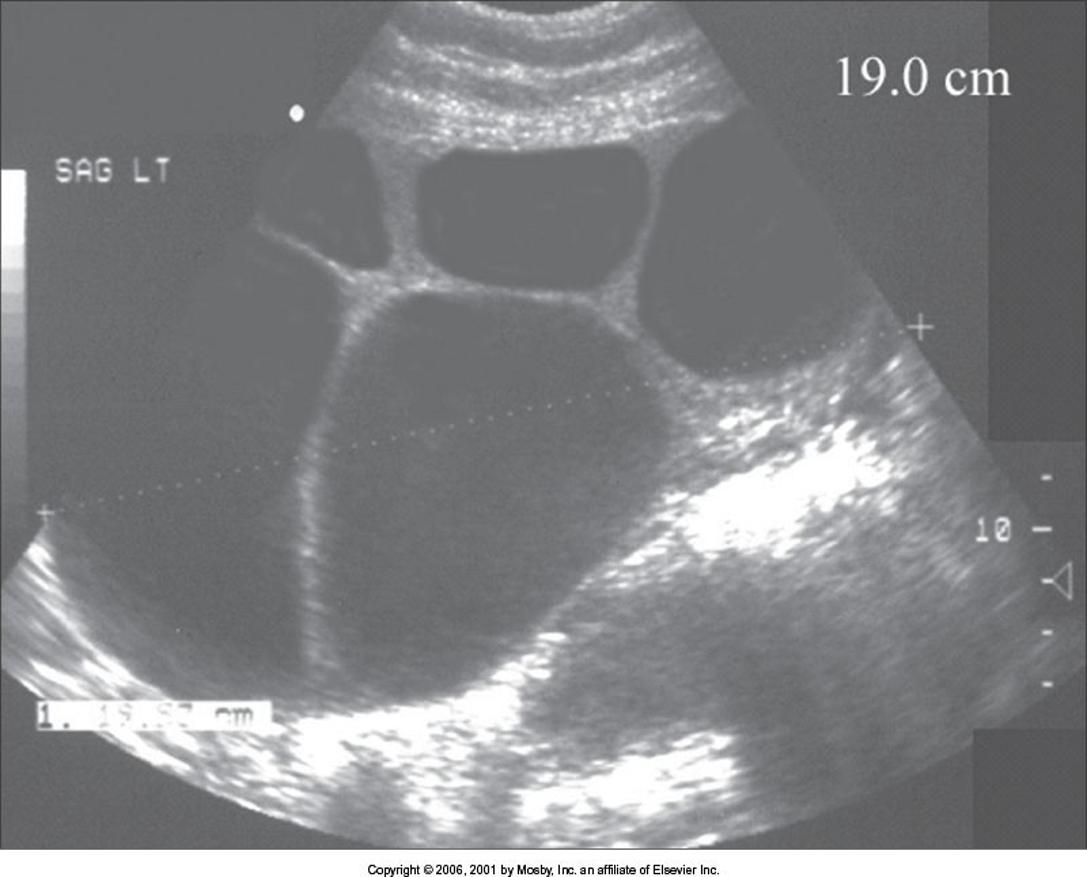

Ovarian Stimulation

Oocyte retrieval

US guided embryo transfer

Ovarian Hyperstimulation Syndrome